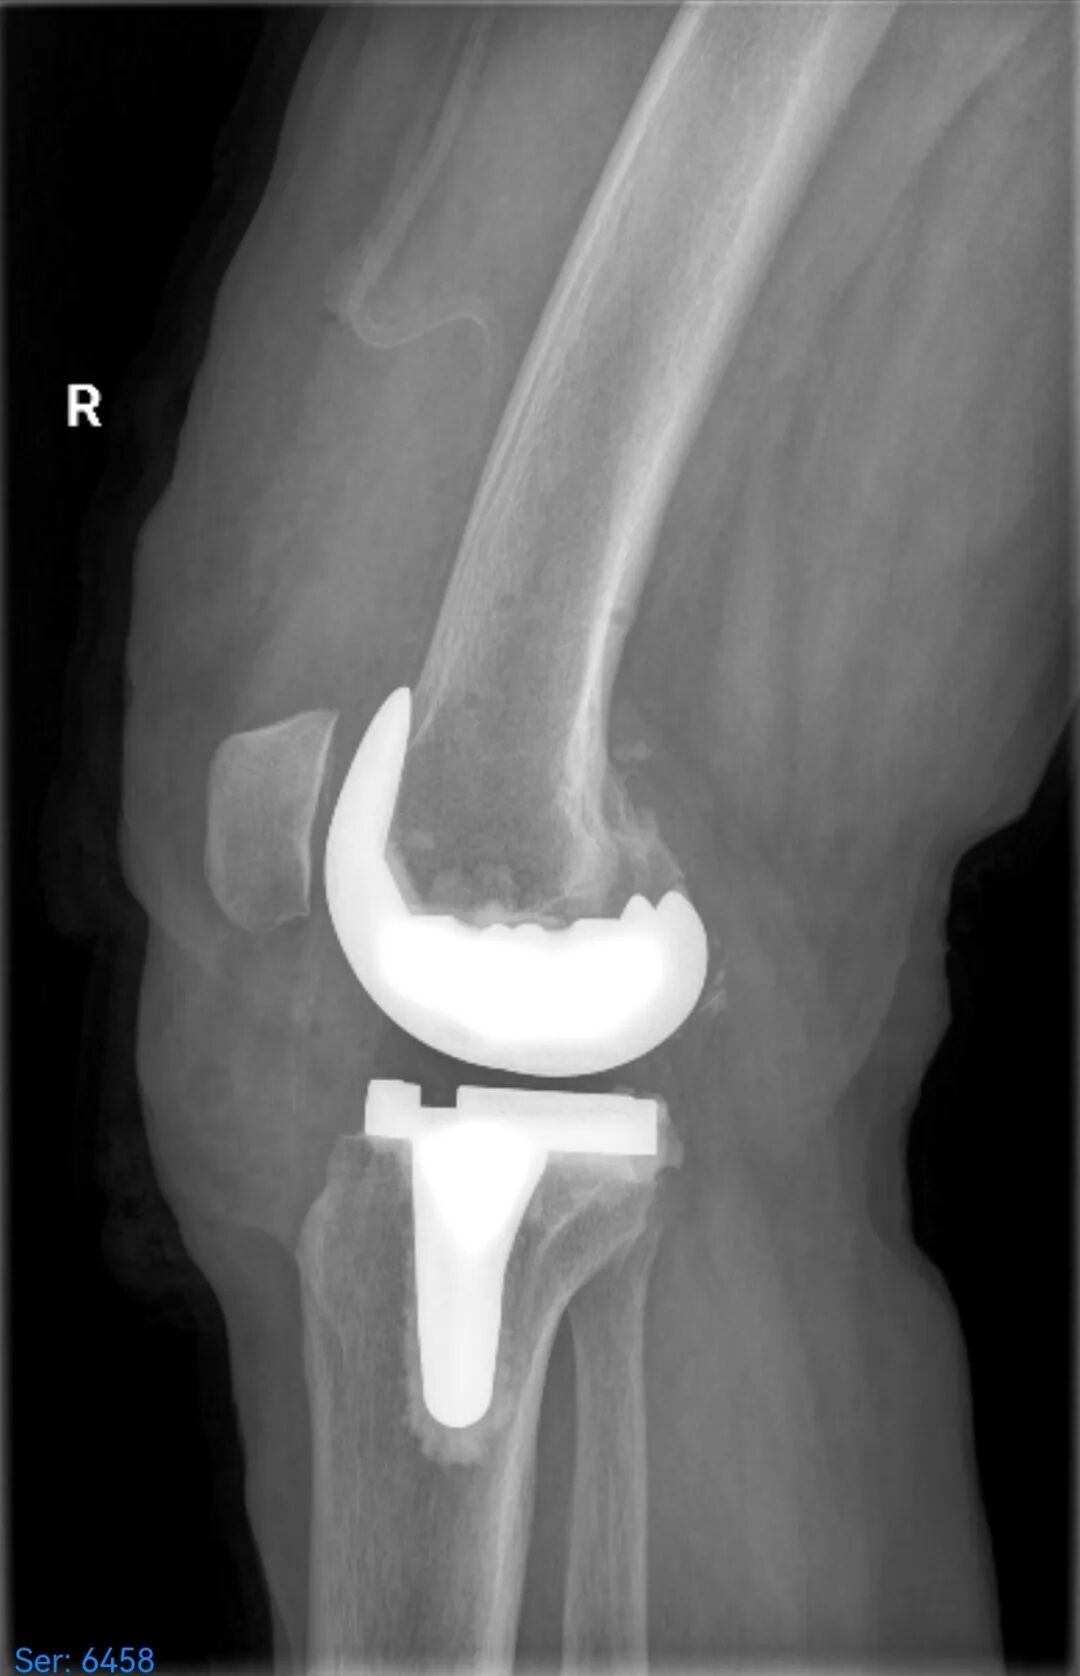

术后

手术过程中,骨三科团队通过操控机械臂实施截骨,操作精度达到毫米级,使得膝关节假体被精准安放在理想位置,由此患者术后下肢力线得以完美恢复。与此同时,这种高精度操作大幅减少了对软组织的松解干扰,不仅显著减轻了患者的疼痛感,还有效降低了术中出血量。

术后第一天,患者在骨三科医护人员的指导下便能下床行走,肢体活动度良好,原有疼痛症状消失。患者及家属对此结果十分满意。在后续的住院期间,骨三科医护团队为患者制定了个性化的康复方案,最终助力患者顺利出院。